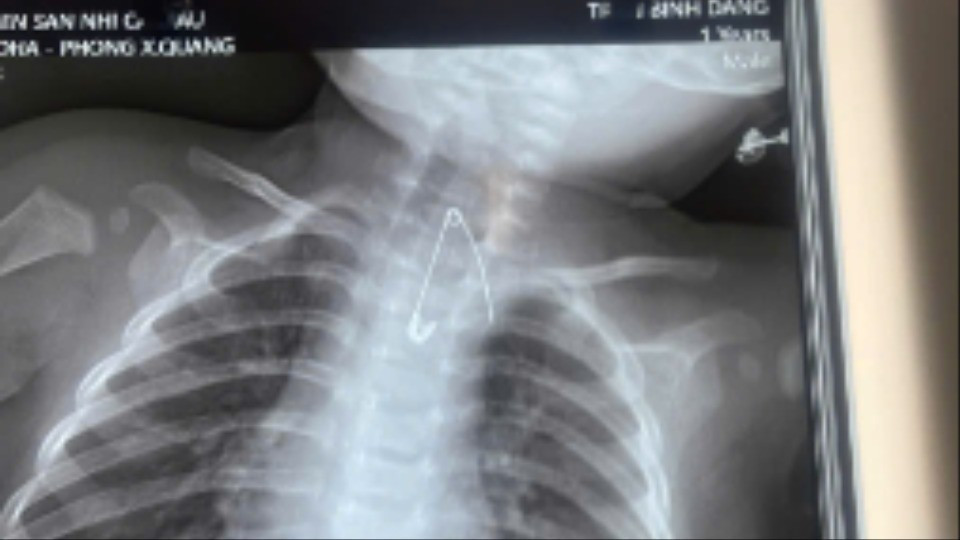

Kim băng nằm sát động mạch chủ bé Đ.

Trường hợp thứ hai là bé trai Đ. (7 tháng tuổi, ngụ xã An Trạch, tỉnh Cà Mau) được gia đình đưa đến bệnh viện trong tình trạng sốt, ho, khò khè kéo dài 2 ngày. Khai thác bệnh sử cho thấy trong khoảng 3 tháng gần đây, bé thường xuyên bị ho, viêm hô hấp tái đi tái lại.

Người nhà cho biết, gia đình có thói quen dùng kim tây (kim băng) ghim bùa bình an vào áo của bé. Qua thăm khám lâm sàng và thực hiện các xét nghiệm cận lâm sàng, các bác sĩ phát hiện một dị vật là kim tây nằm trong mô mềm, ở vị trí sát động mạch chủ, rất nguy hiểm.

Bệnh nhi sau đó được ê-kíp phẫu thuật lấy thành công kim băng, ngăn ngừa các biến chứng nghiêm trọng có thể xảy ra.